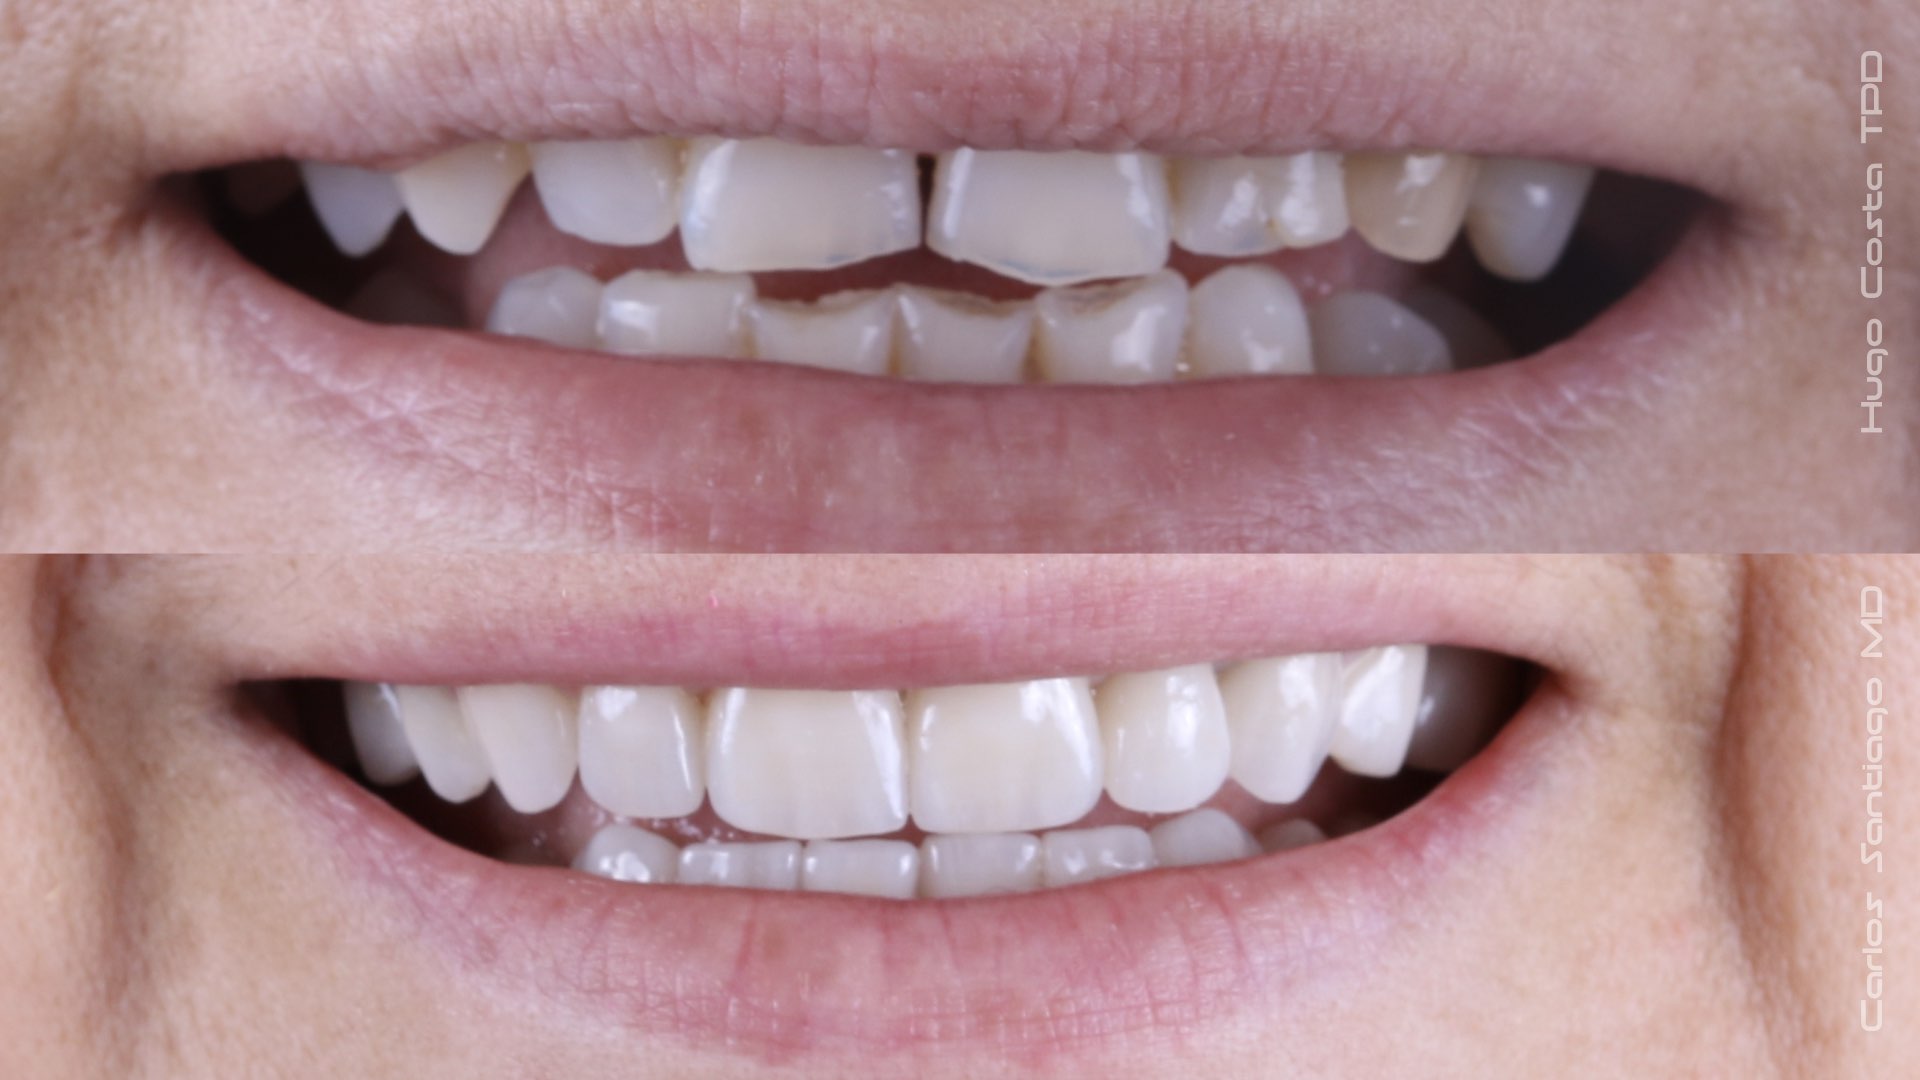

As Facetas Cerâmicas (lentes de contacto dentárias ou laminados), permitem corrigir da maneira mais estética e conservadora possível, problemas de forma e tamanho, côr e posição dos dentes, bem como substituir restaurações antigas e inestéticas.

São aderidas químicamente ao esmalte dentário de uma forma permanente, com o objectivo de melhorar a estética dos nossos pacientes.